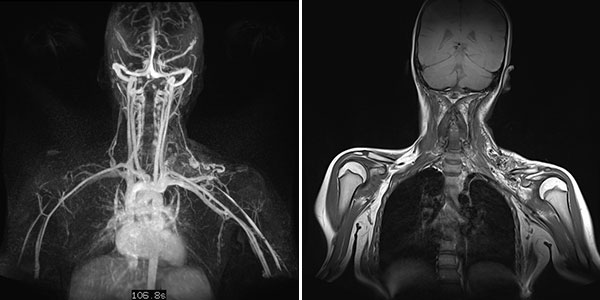

Dynamische, kontrastmittelunterstützte, zeitlich hochaufgelöste MR-Angiographie; Darstellung 46 s nach intravenöser Kontrastmittelapplikation. Das Kontrastmittel hier noch vorwiegend im kleinen Kreislauf der Lunge (Frühphase).

Dynamische, kontrastmittelunterstützte, zeitlich hochaufgelöste MR-Angiographie; Darstellung 52 s nach intravenöser Kontrastmittelapplikation. Bereits 5 s später fließt das Kontrastmittel sofort durch die arteriovenöse Malformation hindurch, eine Drainagevene ist ebenfalls bereits direkt kontrastiert. Typischer, extrem schneller Durchfluss einer arteriovenösen Malformation als Fast-flow-Läsion.

Dynamische, kontrastmittelunterstützte, zeitlich hochaufgelöste MR-Angiographie; Darstellung 57 s nach intravenöser Kontrastmittelapplikation. Weitere 5 s später nochmals bessere Darstellung des venösen Abstroms aus der arteriovenösen Malformation.

In der nativen, T1-gewichteten, koronaren MRT zeigt sich die arteriovenöse Malformation als stark hypointense Raumforderung ohne eigentlich soliden Charakter. Das fehlende MRT-Signal ist durch den schnellen und starken Durchfluss bedingt (sogenannte „Flow-voids“). Das Blut strömt hier so schnell durch die Läsion, dass es kein signalgebendes Echo erzeugen kann.

Dynamische, kontrastmittelunterstützte, zeitlich hochaufgelöste MR-Angiographie (linkes Bild) 5 Tage nach offener Resektion des verschlossenen Nidus; Darstellung wiederum in der Spätphase 107 s nach intravenöser Kontrastmittelapplikation. Auch nach diesem langen Delay zeigt sich keine Restperfusion der arteriovenösen Malformation mehr. Der initial in der koronaren, T1-gewichteten, nativen MRT (rechtes Bild) vormalig noch sichtbare Raumforderungseffekt der AVM ist nach der Resektion verschwunden.